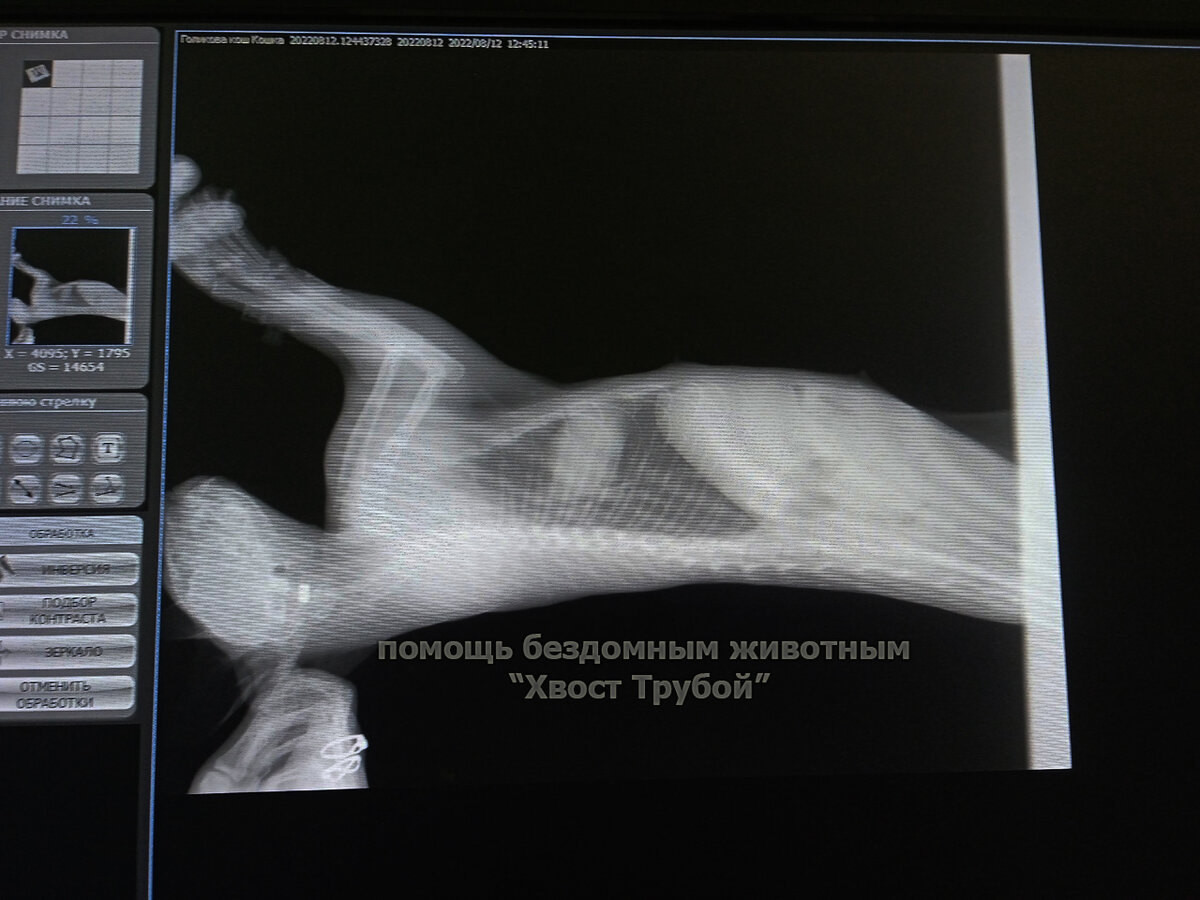

Ей сразу же сделали анализ крови, УЗИ, рентген и оказалось, что дела у малышки из лапок вон плохи. Первое, на что обратили внимание это то, что у кошечки нет глаза. Рентген показал, что в котеечку стреляли и пуля застряла в затылочной части головы. Это просто чудо, что не был задет мозг... Причем судя по характеру травмы, глазика кошечка лишилась давно и с пулей в затылке она живёт, скорее всего, не один месяц.